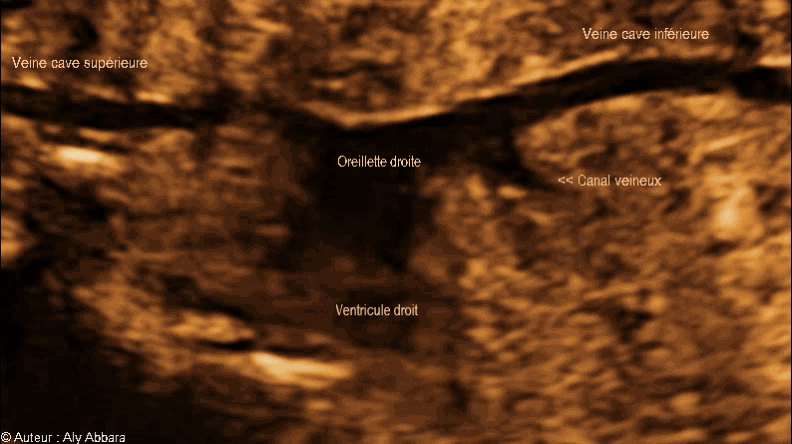

Les deux veines caves, supérieure et inférieure se jetant dans l'oreillette droite - الوريدان الأجوفان، العلوي والسفلي يصبان في الأذينة اليمنى للقلب

Image échographique animée montrant les parties terminales des veines caves (supérieure et inférieure) qui se jettent dans l'oreillette droite du cœur.

Le canal veineux qui prend naissance de la veine ombilicale, après un trajet court, se jette directement dans la partie terminale de la veine cave inférieure au niveau de la terminaison des trois veines hépatiques ; ce site de jonction de la veine cave inférieure avec le ductus veineux et les veines hépatiques se trouve sous le diaphragme et à une distance très courte de l'oreillette droite (quelques centimètres chez l'adulte).

Foetus âgé de 27 SA.